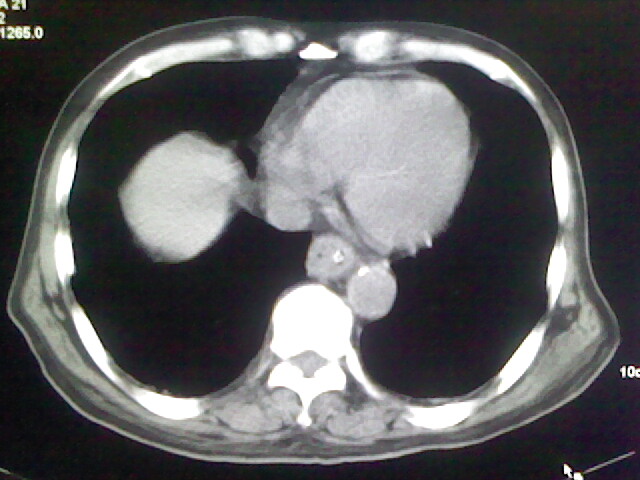

男,70岁,脑出血,长期卧床,左侧背部可触及肿块

右肺病灶考虑炎症性。

右肺病灶考虑炎症性

考虑右肺及左肺下叶炎症。

右肺及左肺下叶炎症。

考虑右肺及左肺下叶慢性炎症。

右侧肺部见片状密度增高影,边缘模糊。考虑炎症。另食管壁增厚。

右肺上叶前段病呈楔形,其尖端指向肺门,考虑肺动脉栓塞可能性大.